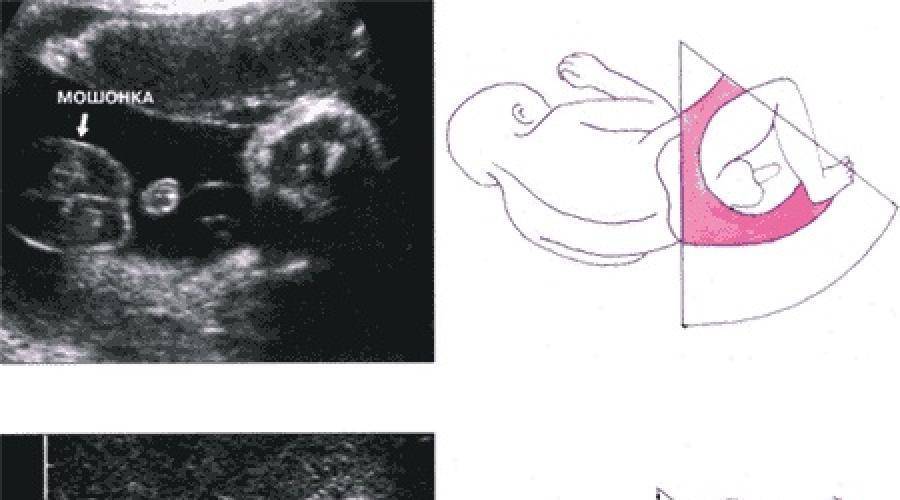

Пол на 14 неделе беременности по узи

Пол на 14 неделе беременности по узи 88 фото